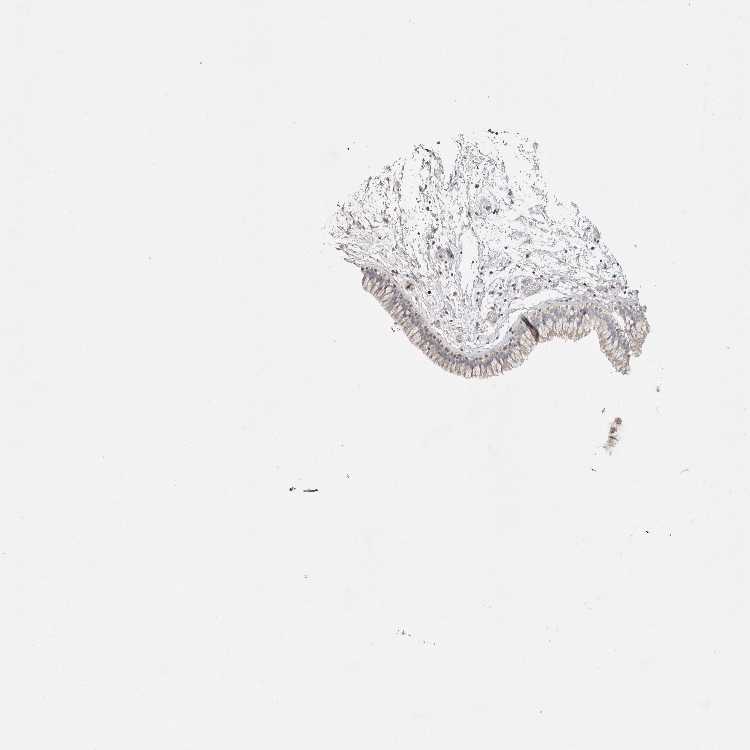

NASOPHARYNX - Antibody stainingi

Antibody staining in the annotated cell types in the current human tissue is reported as not detected, low, medium, or high, based on conventional immunohistochemistry profiling in selected tissues. This score is based on the combination of the staining intensity and fraction of stained cells.

Each image is clickable and will lead to virtual microscopy that enables deeper exploration of all samples and also displays staining intensity scores, fraction scores and subcellular localization as well as patient and tissue information for each sample.

Antibody HPA027603

Respiratory epithelial cells Low